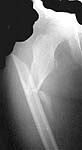

Nice images.

Nice clincial photo.

Great job of "bypass plating".

Very bio-logical.

This patient had 110 degrees hip dynamic screw put in (regular, flat radiolucent table). Although I felt necessary to put the cerclage wire for better reduction, that was done with minimal additional damage and I would still consider it as "bridge plating technique" (the scar length is not crucial determining factor). She was weight bearing as tolerated after 6 weeks (without crutches) and x-rays presented here are after 8 weeks.